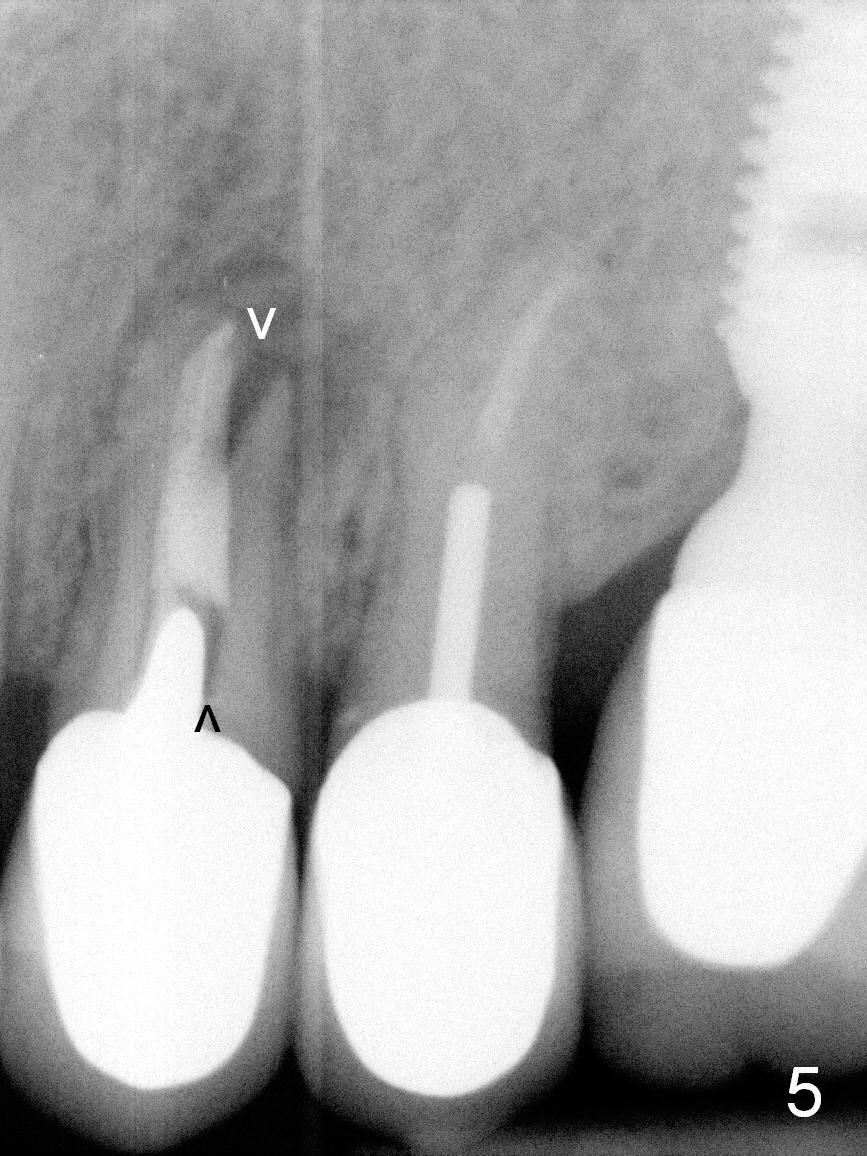

A 57-year-old lady had poor dentition, including periapical radiolucency of the tooth #12, 8 years ago (Fig.1 *, 2007). After comprehensive treatment, the pathology is apparently under control (Fig.2 <, 2011). CBCT shows the pathology not completely resolved (Fig.3,4, coronal section, 2012). Early this year, there was sign of crack tooth at #12 (Fig.5 arrowheads). Last Saturday she returned because of dislodgement of the crown and post. The tooth is found to be non salvageable.

A 4.5x14 mm bone-level or 4.5x17 mm tissue-level implant appears to be appropriate for the site according to the PA (Fig.6,7). CBCT shows that there is enough bone to place a 4.5x20 mm tissue-level implant (Fig.8). This is more appropriate, considering the large radiolucency (Fig.5), the age of the patient (possibly osteoporosis), and the maxilla (bone softer than that of the mandible). The implant will be supported by approximately 8 mm solid bone apically (Fig.8).